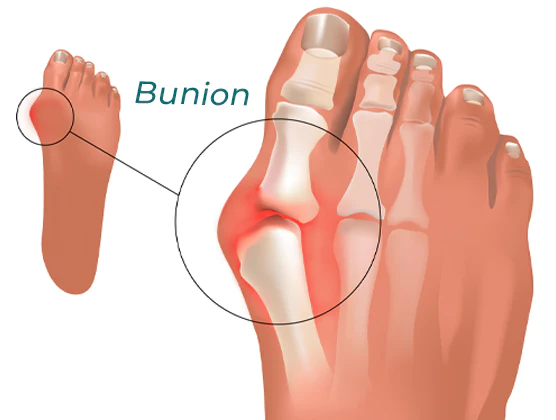

When you have bunions or overlapping toes, long days on your feet can be quite painful. By entering and soothing the underlying tissue to lessen hurting and discomfort, the RASSMAM™ BunionOut Relief Patch can assist in providing that pain relief in a natural way.

- RASSMAM™ BunionOut Relief Patch are made to straighten your big toe and put it back in its proper place. It not only relieves your toe from the pain, swelling, and pressure brought on by bunions, but it also aids in reducing the bunion so that the joint won’t become misaligned once again. Relieve pain and overlapping toes without surgery.